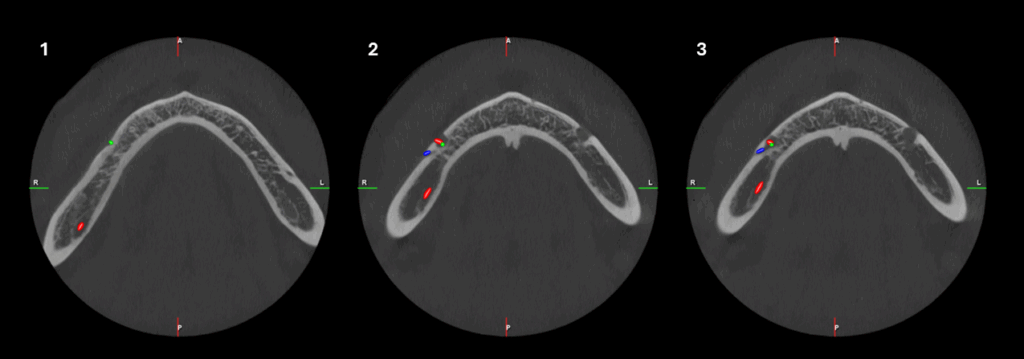

CORTES AXIALES

En la ampliación imagenológica con tomografía computarizada de haz cónico, a nivel del cuerpo mandibular derecho, se identifican forámenes accesorios adicionales al agujero mentoniano principal. Se observa un segundo agujero mentoniano de menor diámetro, ubicado superior al principal, con trayecto cefálico. Además, se identifica un tercer agujero mentoniano localizado en posición distal respecto al foramen principal.